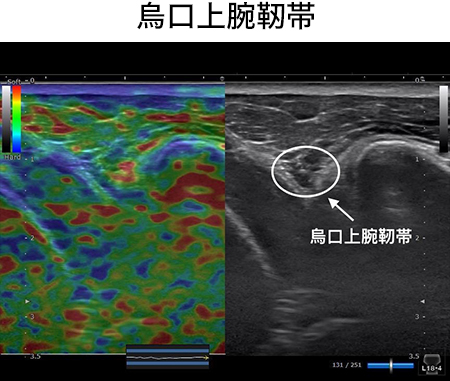

五十肩や肩関節周囲炎の痛みって本当に取り切ることが難しいですよね。よく受講生の皆さんから質問や相談があります。でも正直言って、僕は全然難しいって思ったことがないんですよね。だって、、、この烏口上腕靭帯リリーステクニックでほぼほぼの痛みは取れるから。このテクニックを知ってからは本当に肩の痛み治療が怖くなくなりましたね。あなたが思っている10倍はこの烏口上腕靭帯のせいで痛みや可動域制限がでています。このテクニックを学ぶことであなたは、、、

このセッションを受けることによりあなたは、、、